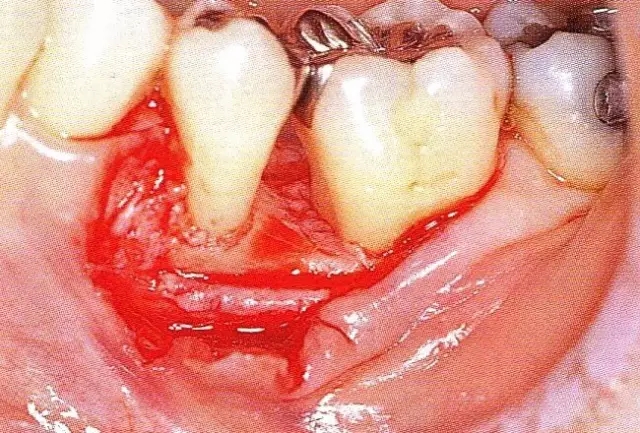

案例3   針對3壁性垂直性骨缺損使用非吸收性膜進(jìn)行再生治療,再翻瓣時進(jìn)行骨形態(tài)修整的病例。

▲圖7-1  左下6近中可觀察到3壁性垂直性骨缺損。此病例考慮到齦瓣供血關(guān)系,在前磨牙部位進(jìn)行了減張切開,沒有進(jìn)行縱切開。并利用刮治器、牙周外科用車針進(jìn)行了徹底的骨缺損部位搔刮。